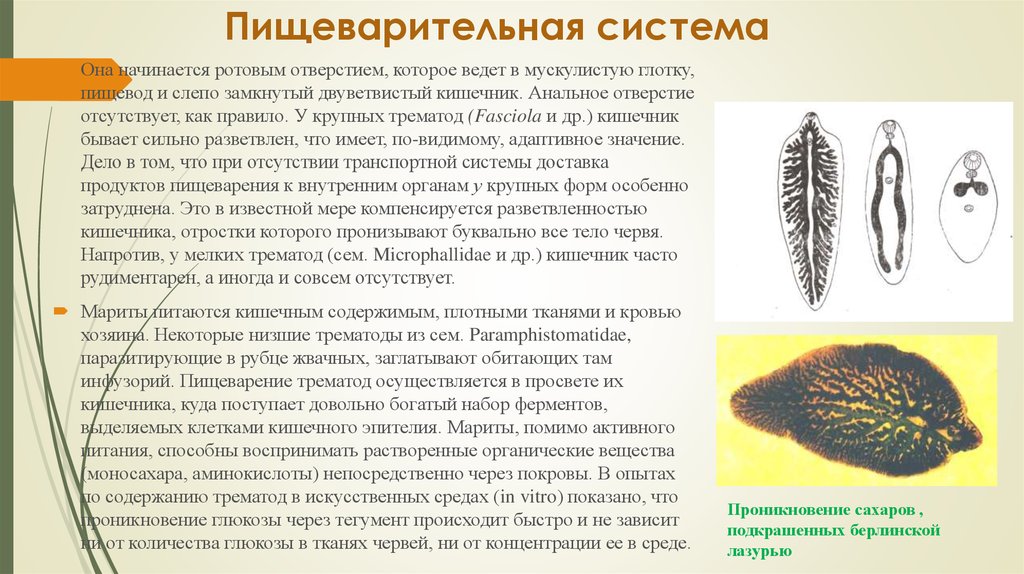

Фотографии нематод, цестод и трематод в природе

Раздел: Другие животные